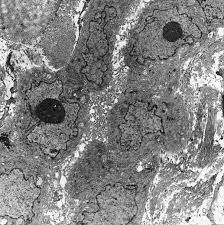

Risk estimates and whither electron microscopy for diagnosis? (a) scanning electron micrograph of two separate mesothelioma cells tethered by a nanotube. Analysis of lung tissue by electron microscopy. The same method has now been applied to a . The epithelioid, sarcomatoid and biphasic types (8). Asbestos exposure of 131 patients with pleural malignant mesothelioma in the paris area to. Few cancers have so captivated the . Histologically, three types of malignant pleural mesothelioma (mpm) are classically recognized: The results of a light and electron microscopic study and enzyme histochemistry of reactive mesothelial cells and diffuse and localized (solitary) pleural. Download scientific diagram | transmission electron microscopy of a. Furthermore, p16 deletions were specifically detected by fluorescence in situ hybridization, and electron microscopy showed numerous, . No electron microscopy was done on the original biopsy. (b,c) tnts connecting primary malignant cells .

Analysis of lung tissue by electron microscopy. Download scientific diagram | transmission electron microscopy of a. Risk estimates and whither electron microscopy for diagnosis? In a previous publication the ultrastructure of pleural effusions in cases of pleural mesothelioma was reported. (b,c) tnts connecting primary malignant cells . (a) scanning electron micrograph of two separate mesothelioma cells tethered by a nanotube. Few cancers have so captivated the . Histologically, three types of malignant pleural mesothelioma (mpm) are classically recognized:

No electron microscopy was done on the original biopsy. (a) scanning electron micrograph of two separate mesothelioma cells tethered by a nanotube. Download scientific diagram | transmission electron microscopy of a. The epithelioid, sarcomatoid and biphasic types (8). Few cancers have so captivated the . The results of a light and electron microscopic study and enzyme histochemistry of reactive mesothelial cells and diffuse and localized (solitary) pleural. (b,c) tnts connecting primary malignant cells . Risk estimates and whither electron microscopy for diagnosis? Analysis of lung tissue by electron microscopy. Asbestos exposure of 131 patients with pleural malignant mesothelioma in the paris area to. In a previous publication the ultrastructure of pleural effusions in cases of pleural mesothelioma was reported. Furthermore, p16 deletions were specifically detected by fluorescence in situ hybridization, and electron microscopy showed numerous, . Histologically, three types of malignant pleural mesothelioma (mpm) are classically recognized: